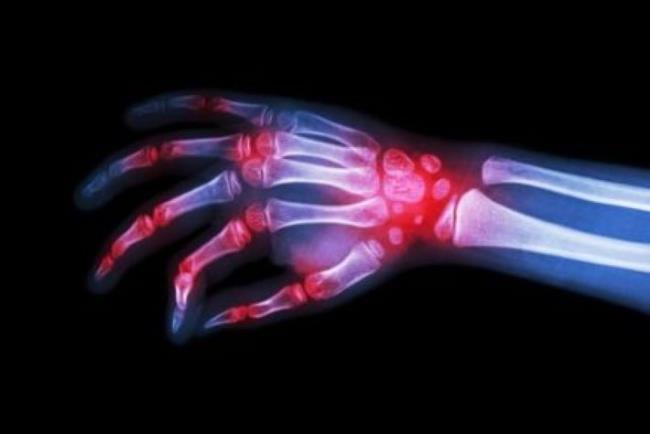

השימוש באינפליקסימב הוא עבור מחלות דלקתיות שמערבות את המערכת החיסונית: דלקת פרקים שגרונית, דלקת כיבית של המעי הגס, דלקת חוליות מקשרות, מחלת קרוהן, ספחת ודלקת פרקים פסוריאטית (שילוב של פסוריאזיס ודלקת פרקים).

צילום: shutterstock